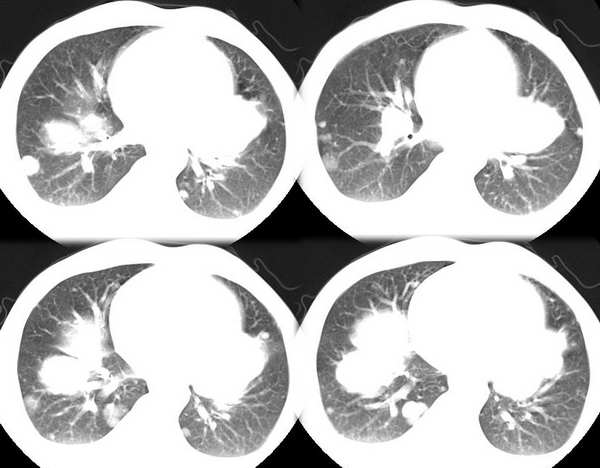

男35y,皮鞋工10余年,近月来发烧,咳血,胸痛,半年前胸片正常,左锁骨上淋巴结肿大,按炎性治疗无效。行ct检查。发平扫片暂无增强片

双肺散在分布多发大小不等圆形、类圆形结节影,多数边界清晰,部分有融合,以肺周边部(胸膜下、隔上及纵隔旁)为著;纵隔肺门淋巴结增大;双侧少量胸水。

影像:两肺散在分布多发大小不等圆形、类圆形结节影,多数边界清晰,部分有融合,纵隔肺门淋巴结增大;双侧少量胸水。

左肺癌(周围型)伴纵隔淋巴结、两肺、胸膜、左锁骨上(临床支持)广泛转移。

影像:两肺散在分布多发大小不等圆形、类圆形结节影,以近胸膜面为明显,多数边界清晰,部分有融合,纵隔肺门淋巴结增大;双侧少量胸水。